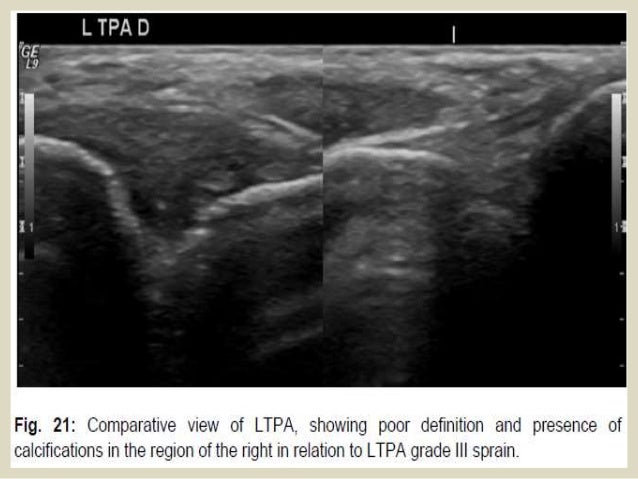

•LIGAMENT INJURIES

The ligament partial tear ligament shows a hypoechoic

areas swollen with internal focal or diffuse. In ...

LATERAL COMPARTMENT

These injuries occur secondary to inversion sprains, with internal rotation of

the foot combined with ...

62. 62. The sindesmosys sprains are up to 10% of ankle injuries, happening in eversion and pronation movements (like the deltoid ligament injury) and primarily affect the anterior tibiofibular ligament (ATFL), the failure is frequently associated with fracture of the fibula. According to the place of employment are 4 degrees, useful for prognostic evaluation and therapeutic strategy choice. Grade I: stretch or partial tear of the ATFL Grade II: complete tearing but only the ATFL Grade III: complete tear of the ATFL and partial CFL Grade IV: complete tear of the ATFL and CFL. The grade I and II injuries usually scarred without any significant instability, whereas grade III and IV injuries can cause chronic pain and require surgical treatment.